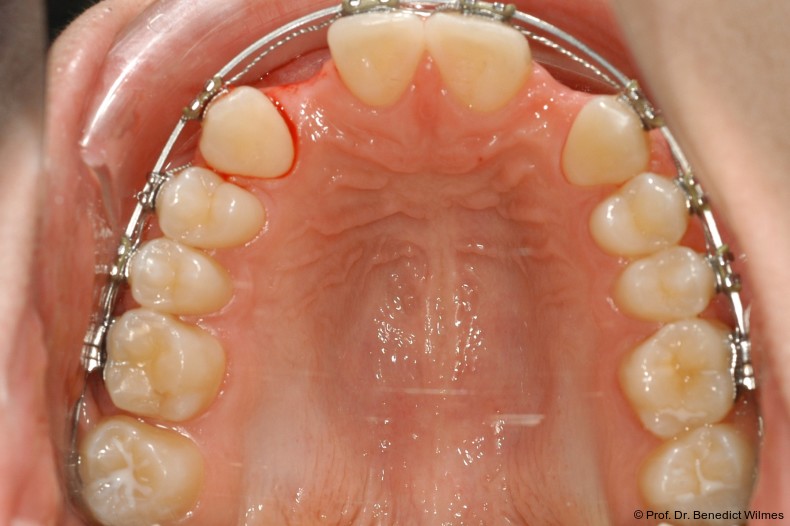

Nach Abschluss der kieferorthopädischen Pfeilerverteilung wurden zwei Miniimplantate in Regio 3er inseriert (2 x 13 mm). Nach Herstellung im Labor wurden Kronen auf den Miniimplantaten aufgeschraubt (Abb. 13+16a–d). Auch hier wurde darauf geachtet, dass die Kronen aus der Okklusion geschliffen wurden (Abb. 14). Bei den Nachkontrollen zeigten sich ebenfalls stabile Miniimplantate und ein entzündungsfreies Implantatlager ohne erkennbare Atrophie des Knochens (Abb. 15 und 16a–d).